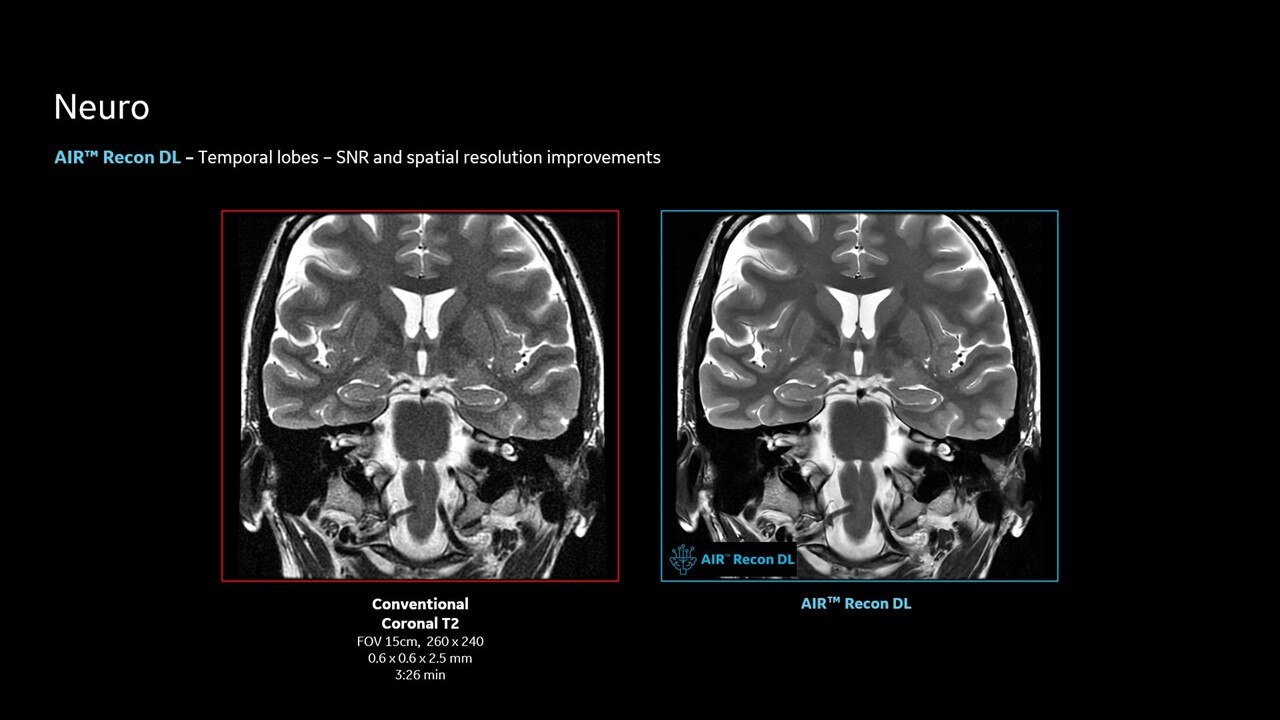

AIR™ Recon DL improves SNR and image sharpness, enabling shorter scan times

Achieve a 25% efficiency gain with Ultra High Efficiency (UHE) gradient system. Fast, clear Total Digital Imaging (TDI) increases SNR by 25%. Improved IQ in 80% of cases without added time. Acquire higher SNR without a time penalty and get images virtually free of artifact with AIR™ Recon DL.***